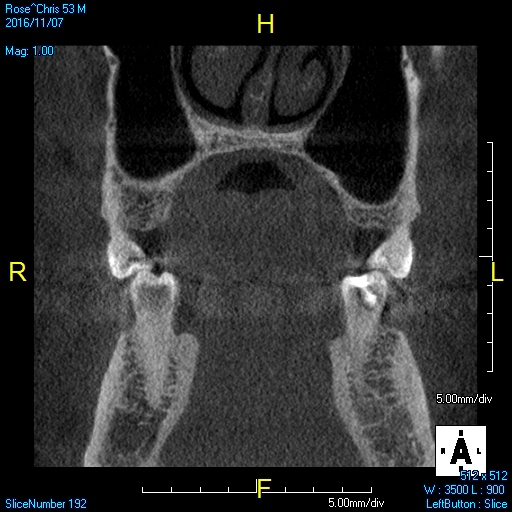

The morphology of the airway can be evaluated with CBCT images. Understanding the length and width of the upper airway is important to assess the pathology and the physiology of OSA and deliver the appropriate treatment therapies that best fit the patient's needs and predict effectiveness of the treatment. Wider and shorter upper airways display less airway resistance than narrow and long upper airways, which have an increase in airway resistance. Increase in airway resistance evokes inflammation of the airway, creating more inflammation and, therefore, increasing the severity of OSA. Figure 1 and Figure 2 display different morphologies in airways, as shown through CBCT imaging.9

Fig 1. Airway morphology.

Figure 1

Fig 2. Airway morphology.

Figure 2